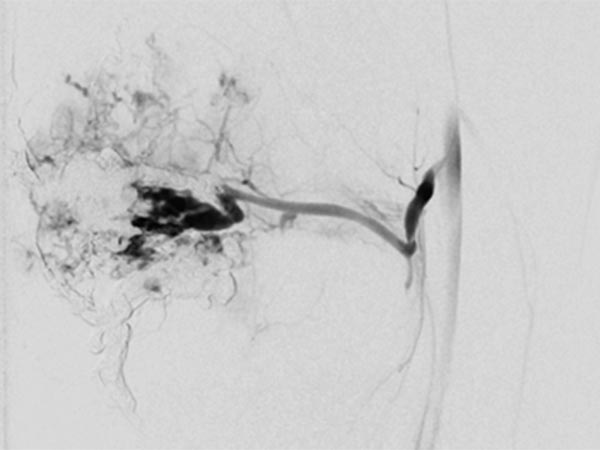

Nach erneuter superselektiver Sondierung der AVM-speisenden Arterie, einer Arteria genu medius lateralis, wird der Mikrokatheter bis unmittelbar vor den Nidus vorgeschoben.

DSA-Bild (roadmap-Technik) während der erneuten Embolisation zeigt schwarz im Bild das frisch injizierte neue, zusätzliche Embolisat.